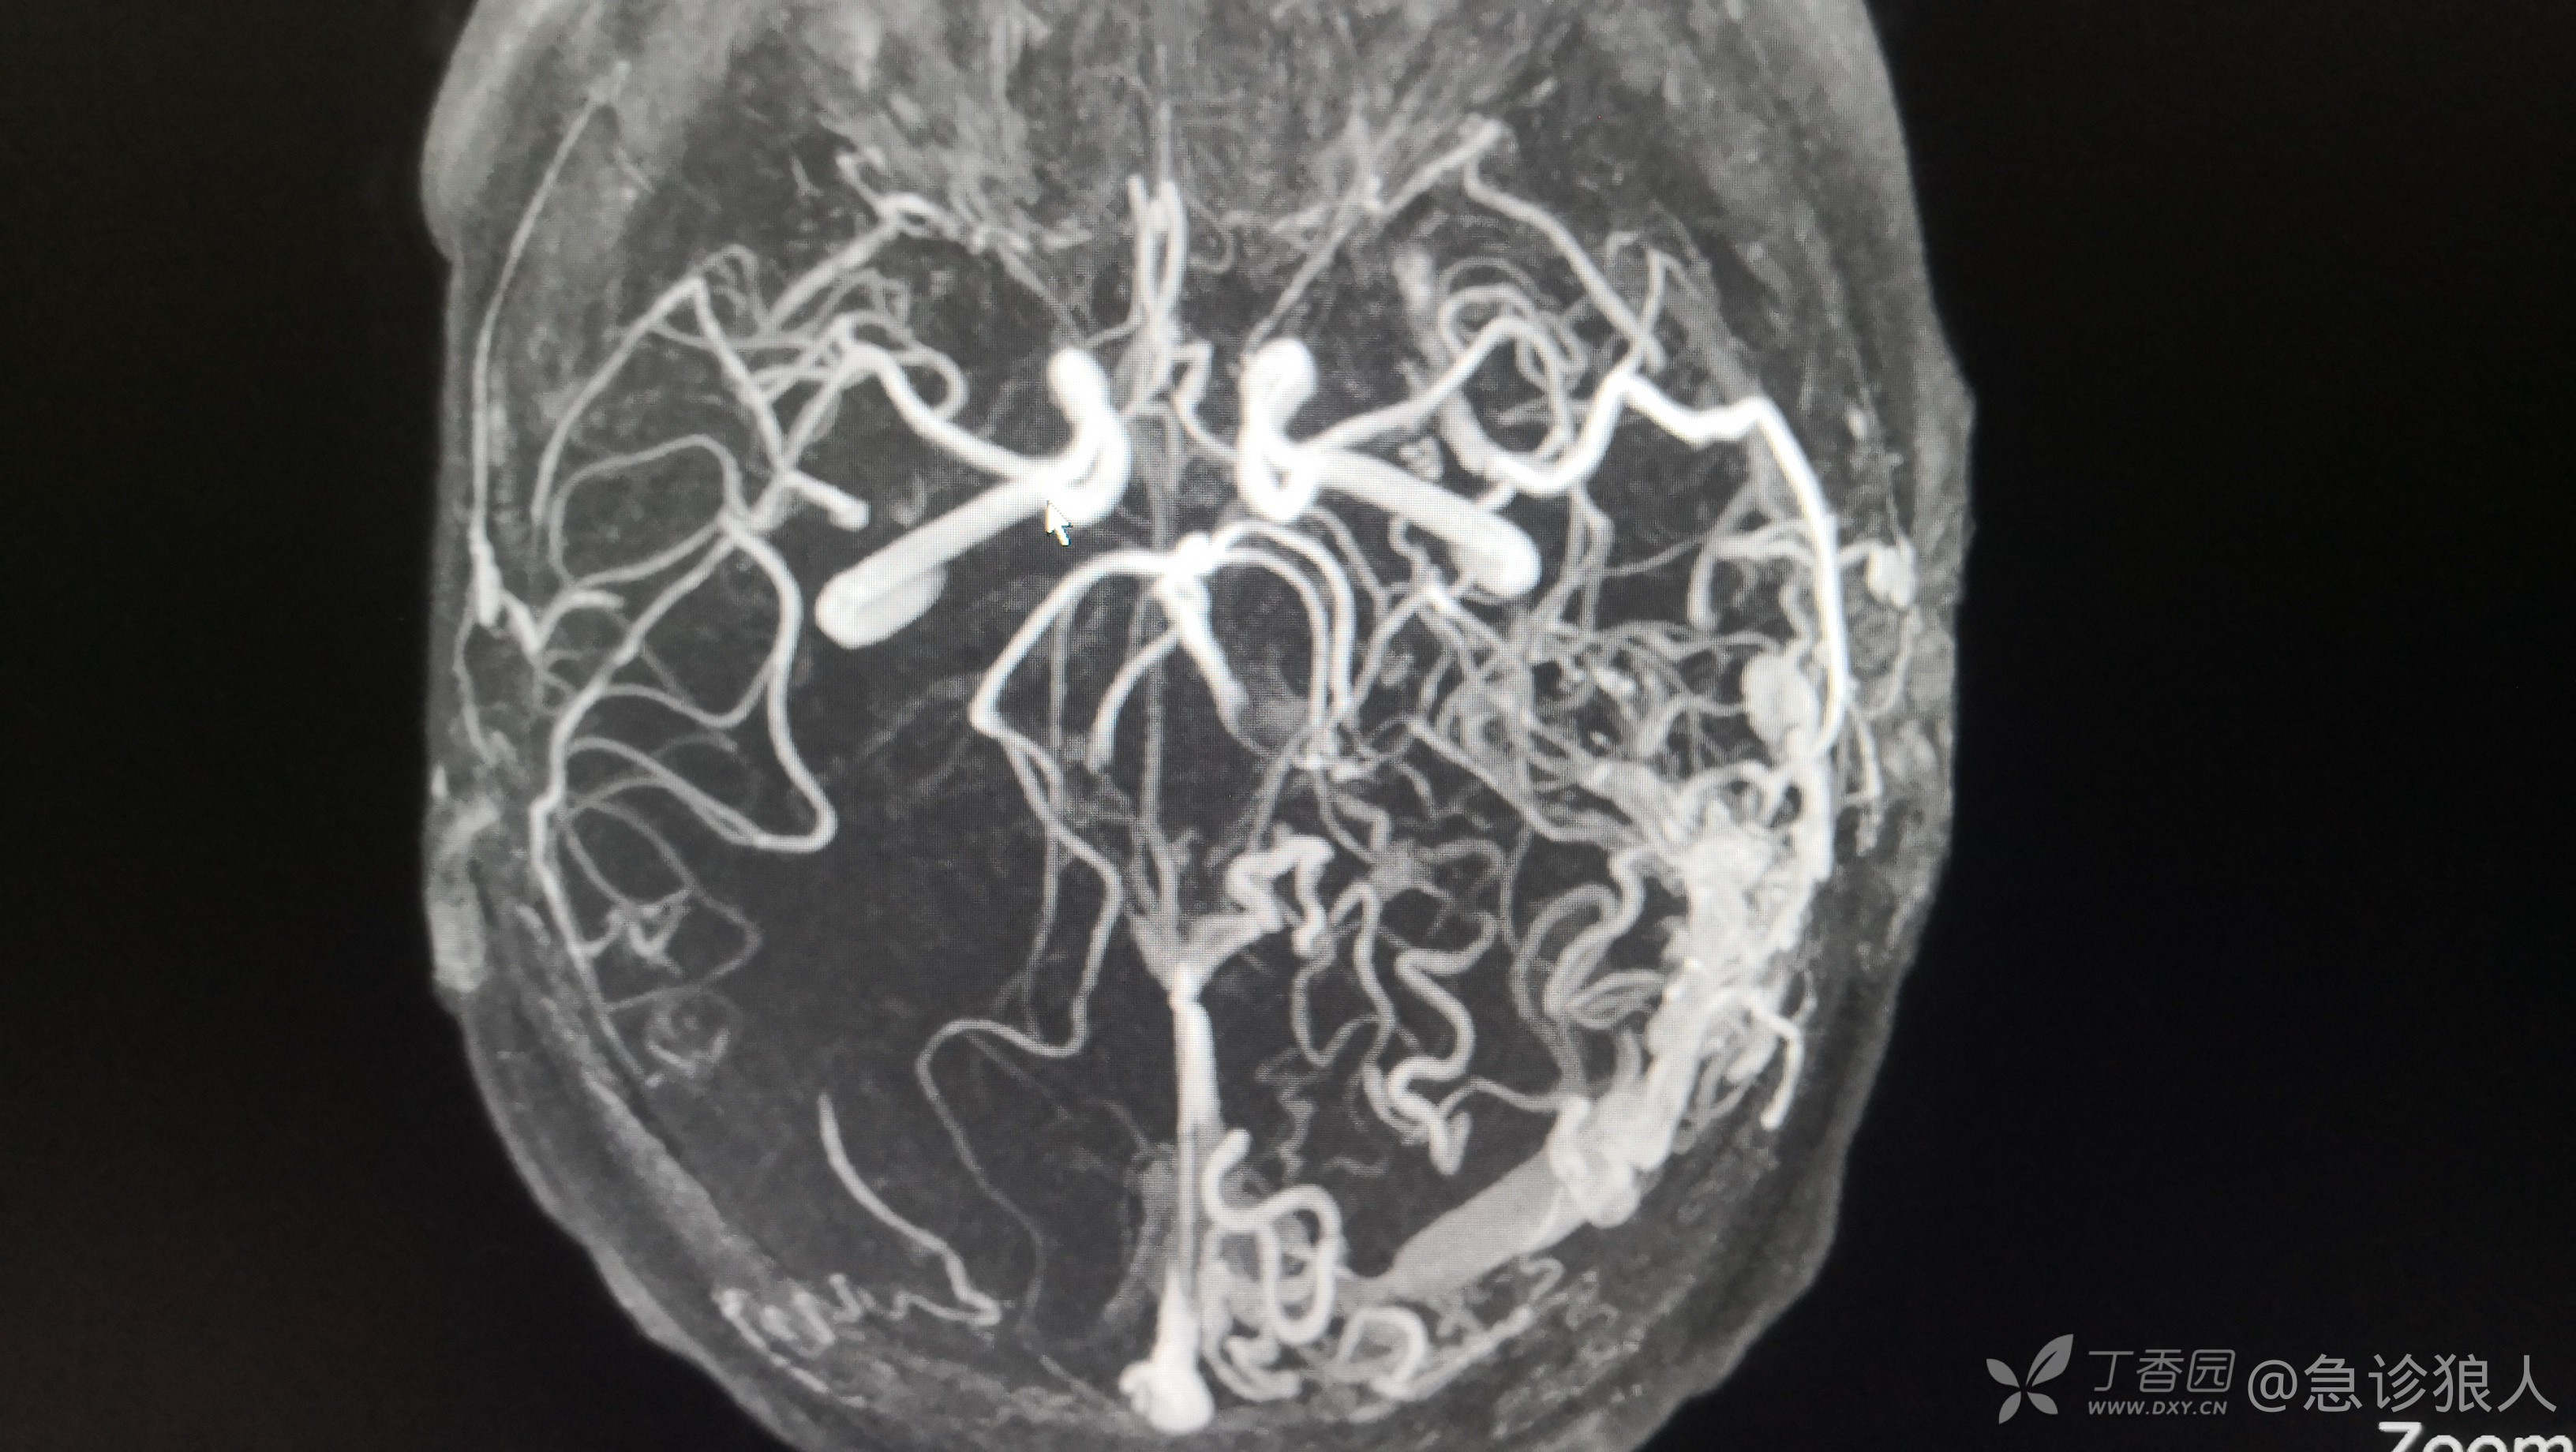

左侧大脑半球多发杂乱,迂曲血管影,与左侧乙状窦相通,考虑硬脑膜动静脉瘘可能性大。

出来结果,神内愿意收了,收上去做了DSA,动静脉瘘修补!